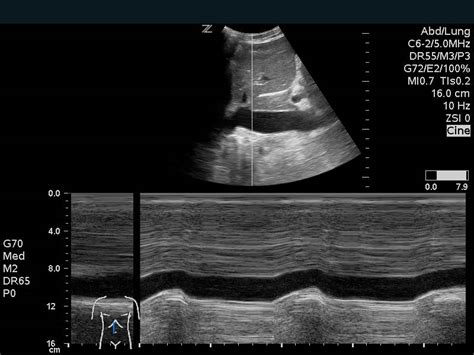

First up, we have Echocardiography . Think of this as an ultrasound of the heart. It uses sound waves to create moving pictures of your heart. It’s non-invasive, meaning there are no needles or anything like that, and it’s super useful for looking at the structure of your heart, how well it’s pumping, and how your valves are working. There are different types of echocardiograms, including transthoracic (where the probe is placed on your chest) and transesophageal (where the probe goes down your throat – a bit more involved, but it gives a clearer picture). Another common type is Electrocardiography (ECG or EKG) is often performed during stress tests to monitor the heart’s electrical activity. This test involves placing electrodes on the patient’s skin to record the heart’s electrical impulses and can provide crucial information on a variety of cardiovascular conditions.